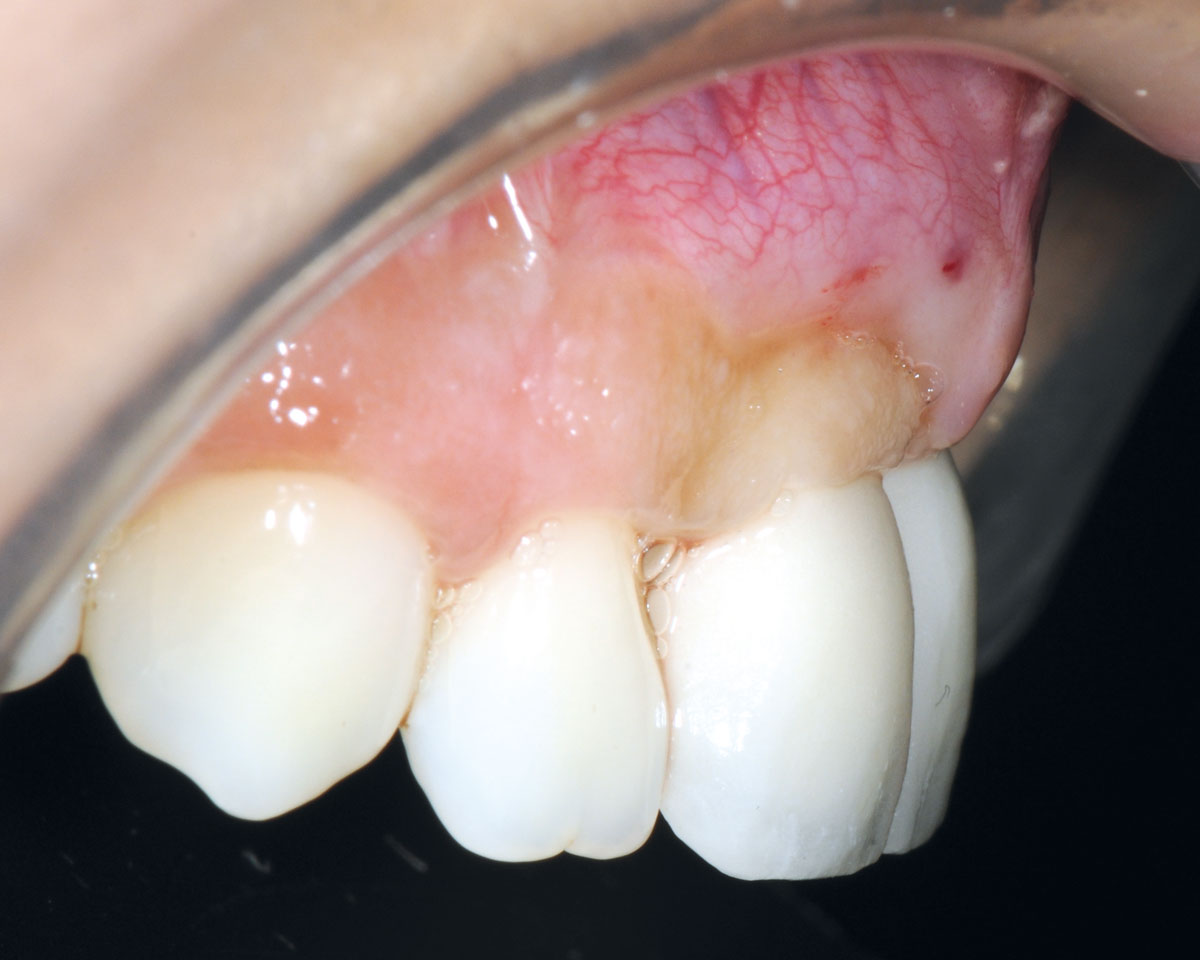

25/26 - Final crowns immediatly after restorationBone augmentation in aesthetic zone with maxgraft® bonering - Dr. A. Patel